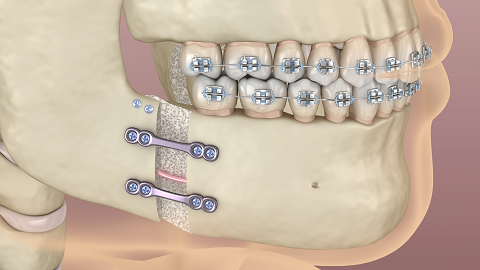

Orthognathic Surgery

Orthognathic surgery, also known as jaw surgery, is performed to address jaw misalignments that may affect function or appearance. It may be considered for conditions such as difficulty chewing or speaking, as well as for facial imbalances. The procedure aims to reposition the jaw to improve bite function and facial symmetry. A thorough evaluation by Orthodontic and Maxillofacial specialists is required to determine if jaw surgery is appropriate for your case.